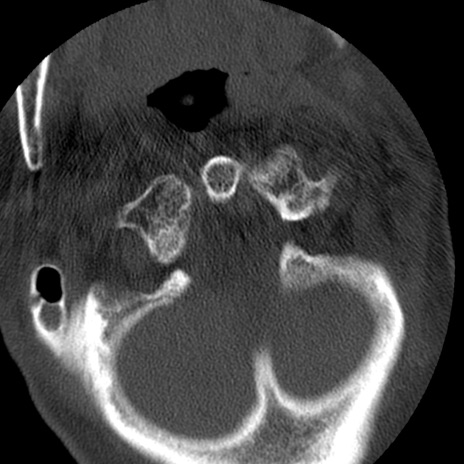

症例50 頚椎CT(横断像)

【症例】60歳代女性

【主訴】後頭部〜右後頸部にかけての痛み

【現病歴】本日飲食店でコーヒーを飲んでいたところ、突然後頭部〜右後頸部にかけて痛みが出現し、右上肢の感覚障害を伴ったため救急要請。

【身体所見】脳神経学的に明らかな異常所見を認めず。右上肢に軽度の感覚障害あり。

異常所見と診断は?

頚椎CT